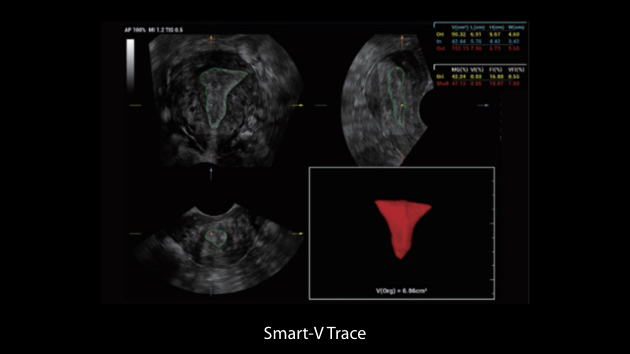

Gambar Klinis